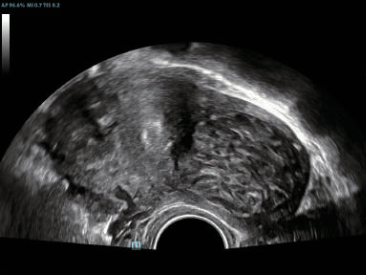

?

–Γ–Ω–Β―Ü–Η–Α–Μ―¨–Ϋ–Ψ ―¹–Κ–Ψ–Ϋ―¹―²―Ä―É–Η―Ä–Ψ–≤–Α–Ϋ–Ϋ―΄–Ι –¥–Α―²―΅–Η–Κ –¥–Μ―è –Ω―Ä–Ψ–≤–Β–¥–Β–Ϋ–Η―è –Η–Ϋ–≤–Α–Ζ–Η–≤–Ϋ―΄―Ö –Ω―Ä–Ψ―Ü–Β–¥―É―Ä –Η –Η―¹―¹–Μ–Β–¥–Ψ–≤–Α–Ϋ–Η–Ι –≤ 2D ―¹ –Φ–Η–Ϋ–Η–Φ–Α–Μ―¨–Ϋ–Ψ–Ι ―¹–Μ–Β–Ω–Ψ–Ι –Ζ–Ψ–Ϋ–Ψ–Ι, –Α ―²–Α–Κ–Ε–Β –Κ–Ψ–Ϋ―²―Ä–Α―¹―²-―É―¹–Η–Μ–Β–Ϋ–Ϋ―΄―Ö –Η―¹―¹–Μ–Β–¥–Ψ–≤–Α–Ϋ–Η–Ι;

?

–ï–≥–Ψ –Κ–Ψ―Ä–Ω―É―¹ ―É–¥–Ψ–±–Ϋ–Ψ ―Ä–Α–Ζ–Φ–Β―â–Α–Β―²―¹―è –≤ ―Ä―É–Κ–Β –Η –Ω–Ψ–¥–¥–Β―Ä–Ε–Η–≤–Α–Β―² –Ω―Ä–Η–Φ–Β–Ϋ–Β–Ϋ–Η–Β ―¹–Ω–Β―Ü–Η–Α–Μ–Η–Ζ–Η―Ä–Ψ–≤–Α–Ϋ–Ϋ–Ψ–Ι –±–Η–Ψ–Ω―¹–Η–Ι–Ϋ–Ψ–Ι –Ϋ–Α―¹–Α–¥–Κ–Η ―¹ –Ω–Ψ–Κ―Ä―΄―²–Η–Β–Φ –Η–Ζ –Ϋ–Α–Ϋ–Ψ–Φ–Α―²–Β―Ä–Η–Α–Μ–Α –¥–Μ―è –Μ–Β–≥–Κ–Ψ–Ι –¥–Β–Ζ–Η–Ϋ―³–Β–Κ―Ü–Η–Η.